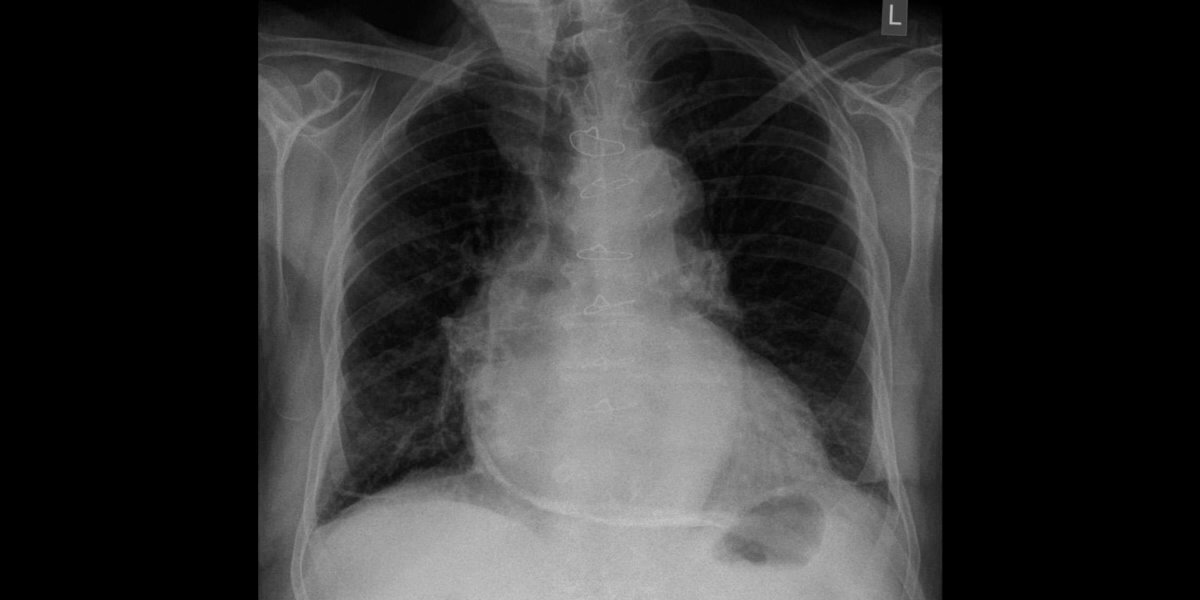

L'hémopéricarde est un épanchement sanguin dans le péricarde qui est la membrane séreuse qui enveloppe le cœur. C'est de fait un épanchement péricardique.

Il est essentiellement clinique. La biologie et l'écho-radiologie en apportent la confirmation.